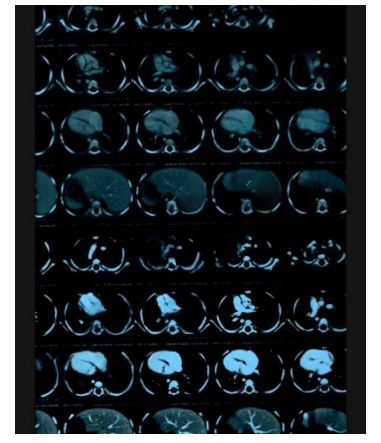

MRI showed: a mass in the posterior mediastinum surrounding the tracheal branch and reaches the diaphragm, surrounding the Azygos vein, superior vena cava, aorta, major vessels and esophagus, measuring (11*5*7) cm. and foci osteolysis in the 9,11,12 thoracic vertebrae.

With an annual periodic review, for blood tests and a chest CT scan that showed a decrease in the size of the lymphangioma.

With an annual periodic review, for blood tests and a chest CT scan that showed a decrease in the size of the lymphangioma